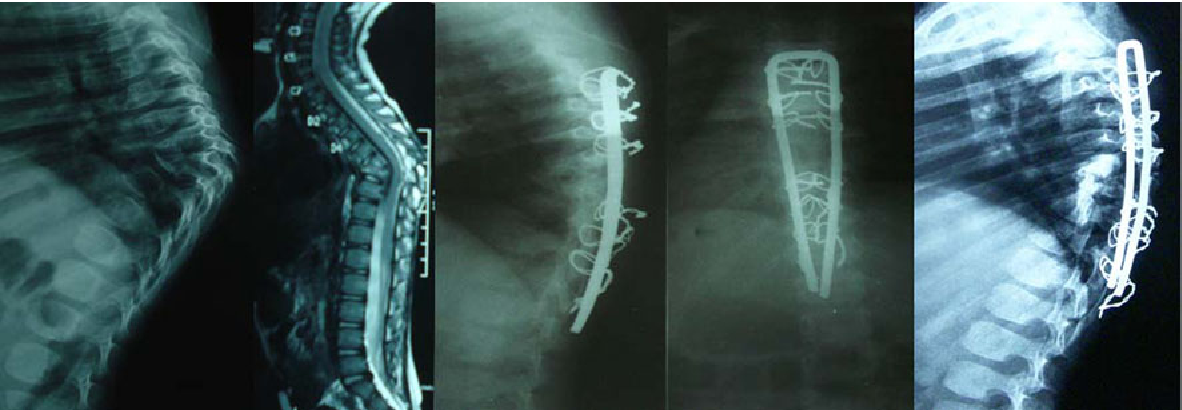

Surgery for spinal tuberculosis typically involved fixation (using Titanium plates or screws and rods), debridement (to clean the infected tissues of the TB bug), biopsy and TB cultures (using BACTEC-MGIT and GENEXPERT as available) and fusion. As against the traditionally held belief, it has been conclusively shown now that there is no problem with using metal work (Titanium) even in cases with active TB infection. Surgery alone cannot treat spinal tuberculosis and it is absolutely necessary to continue anti tuberculosis drug treatment (ATT) as prescribed by your doctor.